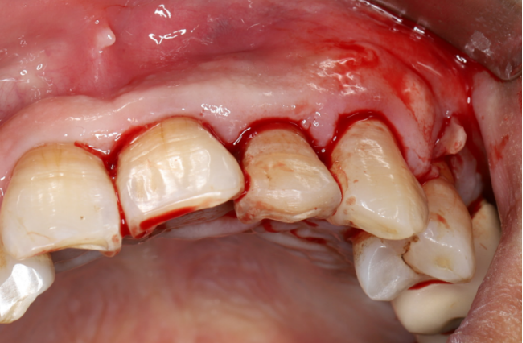

使用12#镰形刀片沿21、22、23做龈沟内切口,于24近中做垂直附加切口。

翻开全厚粘骨膜瓣,暴露22颊侧牙槽骨,微创拔除22。

使用软组织搔刮扩张前后对比:可见在不切断骨膜的前提下,使用软组织搔刮即可获得软组织瓣延长8-9mm。

缝合手术切口

瑞拜欧可吸收生物膜具有一定抗菌活性,复合PRF保护,尝试拔牙创开放愈合,保证了龈乳头原位缝合、避免了膜龈联合位置异位,有利于日后的美学效果,术后常规口腔护理、漱口、服用抗生素5天。